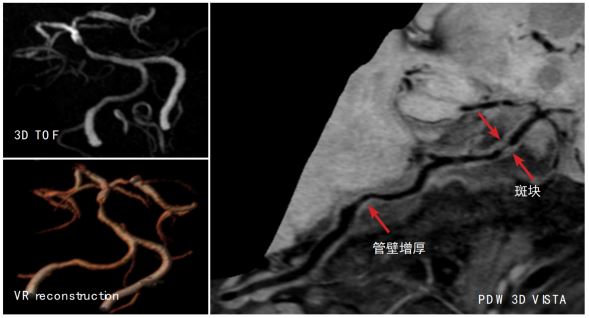

高分辨血管壁成像技术清晰显示椎动脉及基底动脉粥样硬化并斑块形成至管腔狭窄 磁共振高分辨血管壁成像技术显示左侧大脑中动脉 M1 段内血栓致左侧大脑梗塞

磁共振高分辨血管壁成像技术清晰显示左侧大脑中动脉 M1 段炎性增强及管腔狭窄 左侧颈内动脉路外段动脉夹层,可观察到真假腔、内膜片和周围炎性渗出 磁共振大范围高分辨血管壁多对比度成像技术